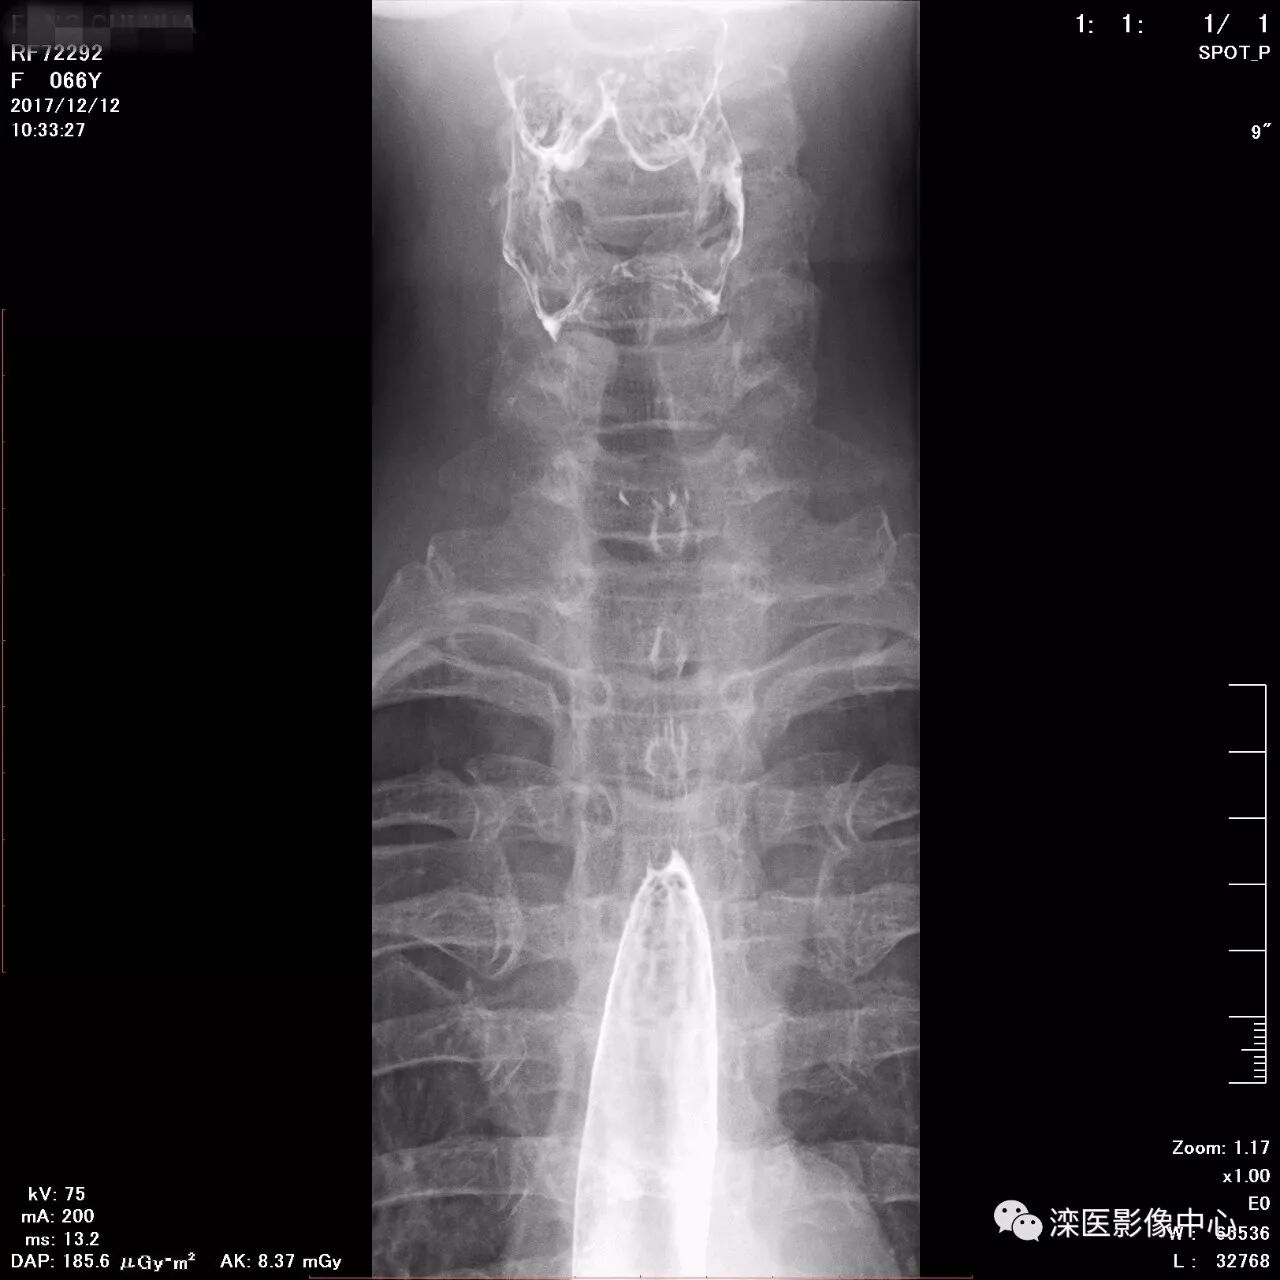

正位,显示食管、贲门及喉咽部的粘膜像)

(左前斜位,显示食管、贲门的粘膜像

(右前斜位,显示食管、贲门的粘膜像)

(以上图像是患者立位+卧位,通过变换体位,多角度显示了贲门胃底、胃体、胃大弯、胃小弯、胃窦、幽门及十二指肠球部、降部、水平部、升部的粘膜像和充盈像。本例患者女性,66岁,此次检查可以清晰显示胃小区结构,检查中发现患有慢性胃炎、胃下垂、十二指肠降部憩室)